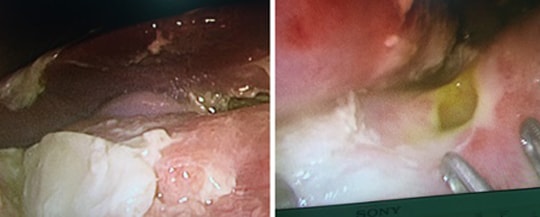

Phát hiện ổ sán lá ruột lớn trong tá tràng bệnh nhân 56 tuổi

(Baonghean.vn) - Vừa qua, các bác sĩ Bệnh viện Quốc tế Vinh đã tiến hành nội soi, gắp ra từ tá tràng của bệnh nhân nữ 56 tuổi nhiều con sán lá kích thước lớn từ 2-3 cm.